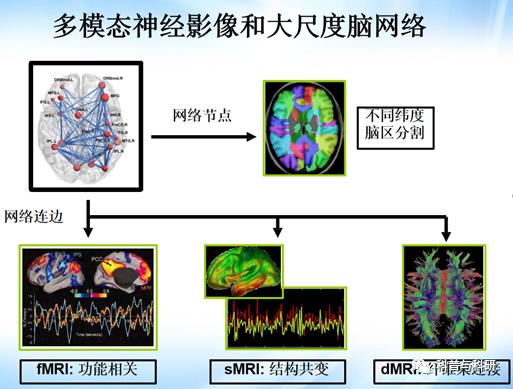

1、静息态独立成分分析(ICA) 2、局部相关,全脑相关,径向相关,径向相似性等指标计算 3、大尺度脑网络功能连接计算 4、CONN工具箱各指标的统计分析 5、各个指标的结果呈现 6、CONN工具箱各个指标手把手实操练习 |

1、静息态功能磁共振分析方法概论 2、静息态功能磁共振分析方法预处理(如时间矫正、头动矫正、标准化、平滑) 3、数据去噪 4、局部指标理论介绍 5、网络指标理论介绍 |

1、静息态功能连接分析 2、动态功能连接分析(简单演示) 3、静息态独立成分分析(ICA) 4、局部相关,全脑相关,径向相关,径向相似性等指标计算 5、ALFF/fALFF等指标计算 6、图论分析 |

基于多模态磁共振影像的人脑连接组学介绍 |

1、人脑连接组学介绍 2、结构网络、功能网络构建介绍 3、基于GRETNA 的静息态 fMRI 数据预处理实操及注意事项 |

基于静息态 fMRI 的 脑功能网络构建 |

1、基于GRETNA 静态功能网络构建 2、脑网络拓扑属性介绍 3、脑网络拓扑属性计算 |